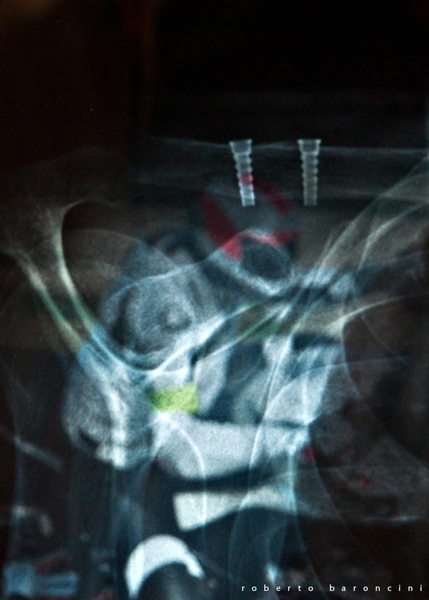

Una radiografia della mia spalla dopo l'intervento, illuminata dal monitor che riproduce una mia foto in azione a Misano.

la proiezione dovrebbe essere quella di "Lamy" detta anche "outlet view" che si esegue spesso per interventi sulla componente ossea coracoidea: (resezione, trasposizione e fissazione con viti) oppure per conflitti muscolo tendinei della spalla...

Il dott. Porcellini mi ha stabilizzato la spalla, resa instabile da una L.A.C. di 4° grado, con un "tendine" sintetico fissato dalle due viti che si vedono nella radiografia.